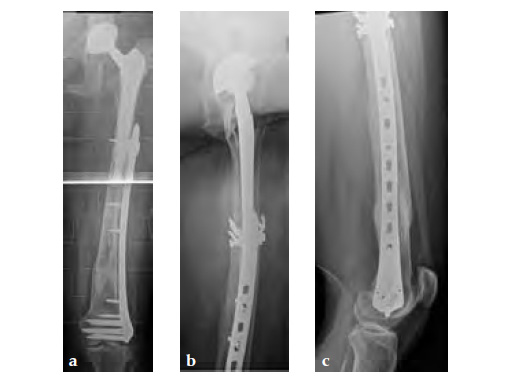

Case 2: A 76-year-old female with a Vancouver type C fracture.